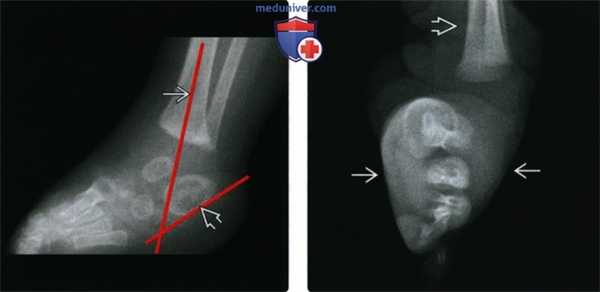

(Слева) Рентгенография в боковой проекции: у пациента с косолапостью определяется варусная деформация заднего отдела стопы. Продольные оси таранной и пяточной костей расположены почти параллельно: угол между ними равен 0°. В норме величина таранно-пяточного угла в боковой проекции у новорожденных составляет 23-55°.

(Справа) При рентгенографии в ПЗ проекции у этого же пациента визуализируется почти параллельное расположение таранной и пяточной костей (угол между ними равен 5°), что указывает на варусную деформацию заднего отдела стопы. В норме величина таранно-пяточного угла в ПЗ проекции у новорожденных составляет 27-56°. (Слева) в боковой проекции: определяется типичная для косолапости деформация переднего отдела стопы. Нагрузка на стопу симулирована. Плюсневые кости расположены друг над другом без какого-либо перекрытия. 1-я плюсневая кость занимает крайнее дорсальное положение, а 5-я плюсневая кость (обведена) расположена ближе всего к подошвенной поверхности стопы.

(Справа) Рентгенография в ПЗ проекции, тот же случай: визуализируется типичная для косолапости деформация переднего отдела стопы. Плюсневые кости приведены, а их основания накладываются друг на друга больше, чем обычно (обратите внимание на оси плюсневых костей).